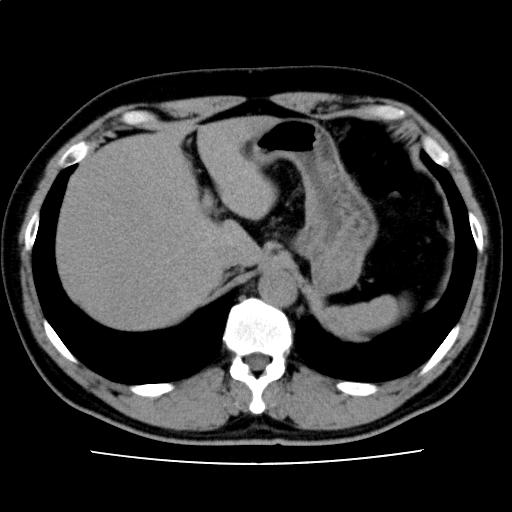

症例画像12

画像診断検査結果12

【画像診断検査結果】

CTスライス画像

(Findings)

脂肪肝を認める。

肝内に明らかな腫瘤性病変を認めない。

胆嚢、膵、脾、副腎、腎に明らかな病的所見を認めない。

傍大動脈および骨盤内にリンパ節腫大を認めない。

腹水を認めない。

(Impression)

脂肪肝

(74/93)